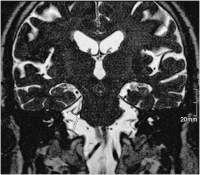

Nervus trigeminus - Arteria cerebelli superior

Abbildung 2: Der Pfeil markiert den Nervus trigeminus rechts im Bereich der Eintrittszone im Hirnstamm. Kranial und lateral wird der Nerv von einer Gefäßschlinge der Arteria cerebelli superior komprimiert.

Keywords: Arteria cerebelli superiorMRTNervus trigeminusNeurochirurgie